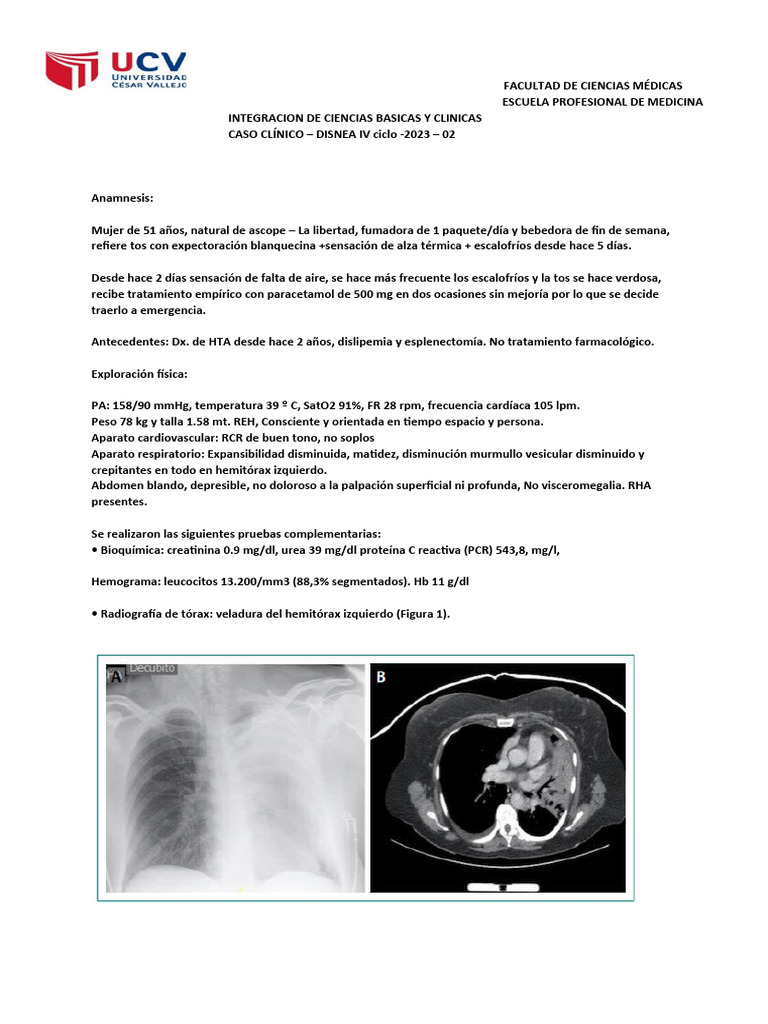

Aparato respiratorio: Expansibilidad disminuida, matidez, disminución murmullo vesicular disminuido y

crepitantes en todo en hemitórax izquierdo.

• Radiografía de tórax: veladura del hemitórax izquierdo (Figura 1).